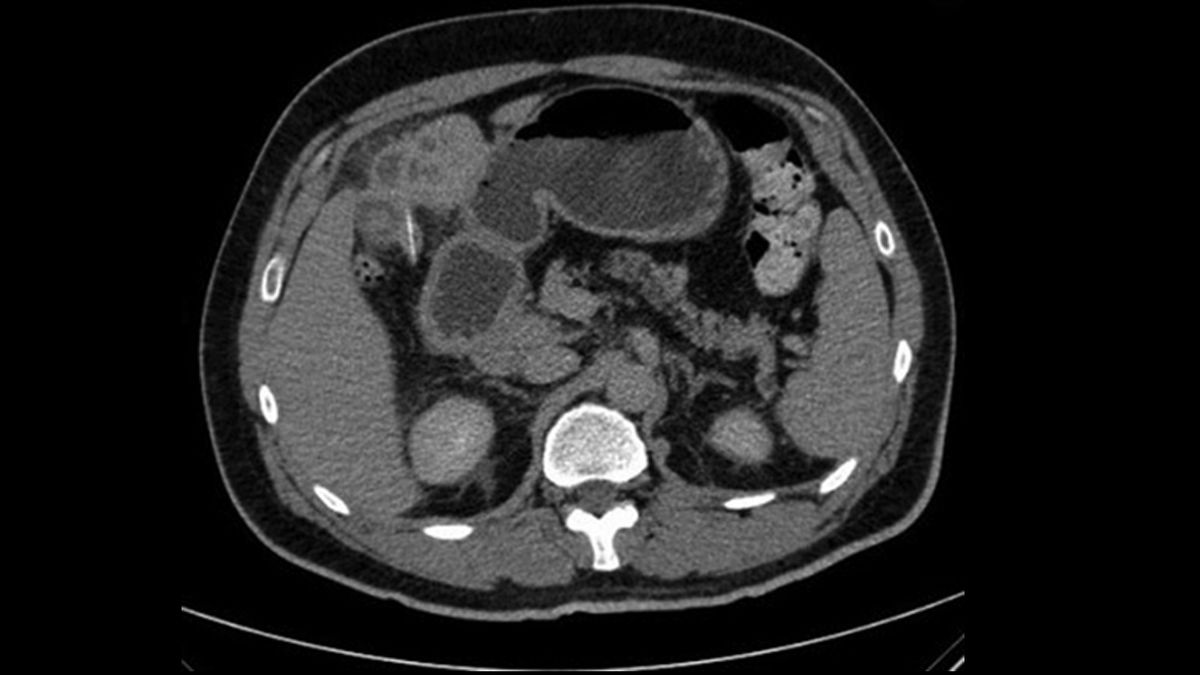

What happened next: During the man’s second hospital visit, blood tests showed that he had an elevated count of white blood cells, a type of immune cell that fights infections, and lower-than-average levels of albumin, a protein produced in the liver. Doctors conducted an abdominal X-ray but detected no abnormalities. A computed tomography (CT) scan of the patient’s abdomen showed that his kidneys, spleen, pancreas and gallbladder looked normal, the doctors wrote in a report of the case.

However, when the medical team examined the central region of the patient’s liver, they found two anomalies. One was a lesion that looked like an abscess, and the other was a solid, twig-like object inside that lesion measuring about 1 inch (2.5 centimeters) long.